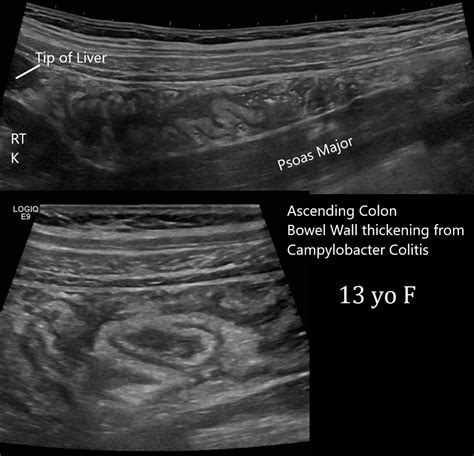

- Infections: Bacterial, viral, or parasitic infections (such as gastroenteritis) can cause temporary, acute wall thickening due to the body's immediate inflammatory response.

- bowel wall thickening ultrasound

- bowel wall thickening radiology